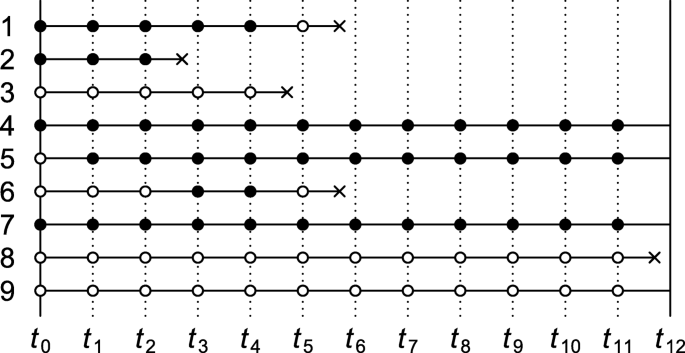

Figure: Schematic diagram of case-control study design. Kenneth F. Schulz and David A. Grimes (2002) Case-control studies: research in reverse . The Lancet Volume 359, Issue 9304, 431 – 434

It is important to note that, unlike cohort studies, case-control studies do not follow subjects through time. Cases are enrolled at the time they develop disease and controls are enrolled at the same time. The exposure status of each is determined, but they are not followed into the future for further development of disease.

As with cohort studies, case-control studies can be prospective or retrospective. At the start of the study, all cases might have already occurred and then this would be a retrospective case-control study. Alternatively, none of the cases might have already occurred, and new cases will be enrolled prospectively. Epidemiologists generally prefer the prospective approach because it has fewer biases, but it is more expensive and sometimes not possible. When conducted prospectively, or when nested in a prospective cohort study, it is straightforward to select controls from the population at risk. However, in retrospective case-control studies, it can be difficult to select from the population at risk, and controls are then selected from those in the population who didn't develop disease. Using only the non-diseased to select controls as opposed to the whole population means the denominator is not really a measure of disease frequency, but when the disease is rare , the odds ratio using the non-diseased will be very similar to the estimate obtained when the entire population is used to sample for controls. This phenomenon is known as the r are-disease assumption . When case-control studies were first developed, most were conducted retrospectively, and it is sometimes assumed that the rare-disease assumption applies to all case-control studies. However, it actually only applies to those case-control studies in which controls are sampled only from the non-diseased rather than the whole population.

Retrospective and Prospective Case-Control Studies

Students usually think of case-control studies as being only retrospective, since the investigators enroll subjects who have developed the outcome of interest. However, case-control studies, like cohort studies, can be either retrospective or prospective. In a prospective case-control study, the investigator still enrolls based on outcome status, but the investigator must wait to the cases to occur.